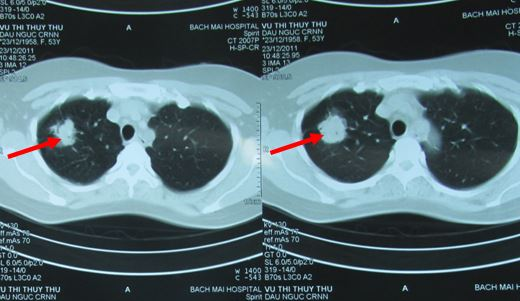

- Chụp CT scanner lồng ngực:

Hình 1: Hình ảnh chụp CT phổi trước điều trị cho thấy u phổi phải kích thước 3,4cm, ngấm thuốc mạnh sau tiêm